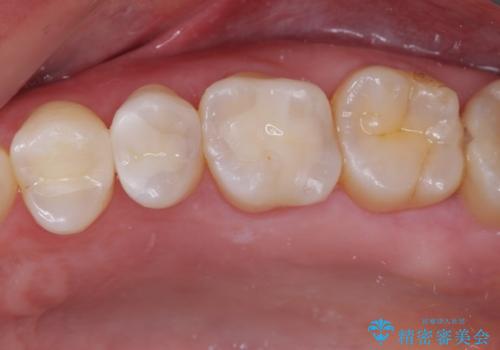

そして次の来院時、セラミックインレーを装着し、噛み合わせなどの調整を行います。

インレーを装着するときは、唾液や血液による接着力の低下を避けるためにラバーダム防湿を行いました。

自然な色調で大変満足されました。